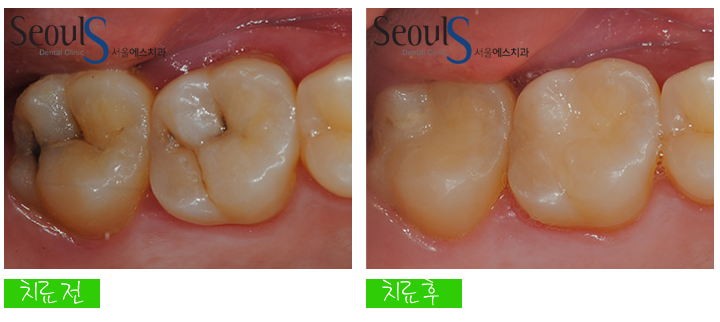

치료는 초기의 경우 충치제거 후 치아색으로 때웁니다

충치 제거 후 치아색으로 때웠습니다

예쁘게 치료된 모습이죠^^

치료 전후 모습입니다

치아 씹는면 충치, 충치제거 후 치아색으로 때워 치료를 마쳤습니다